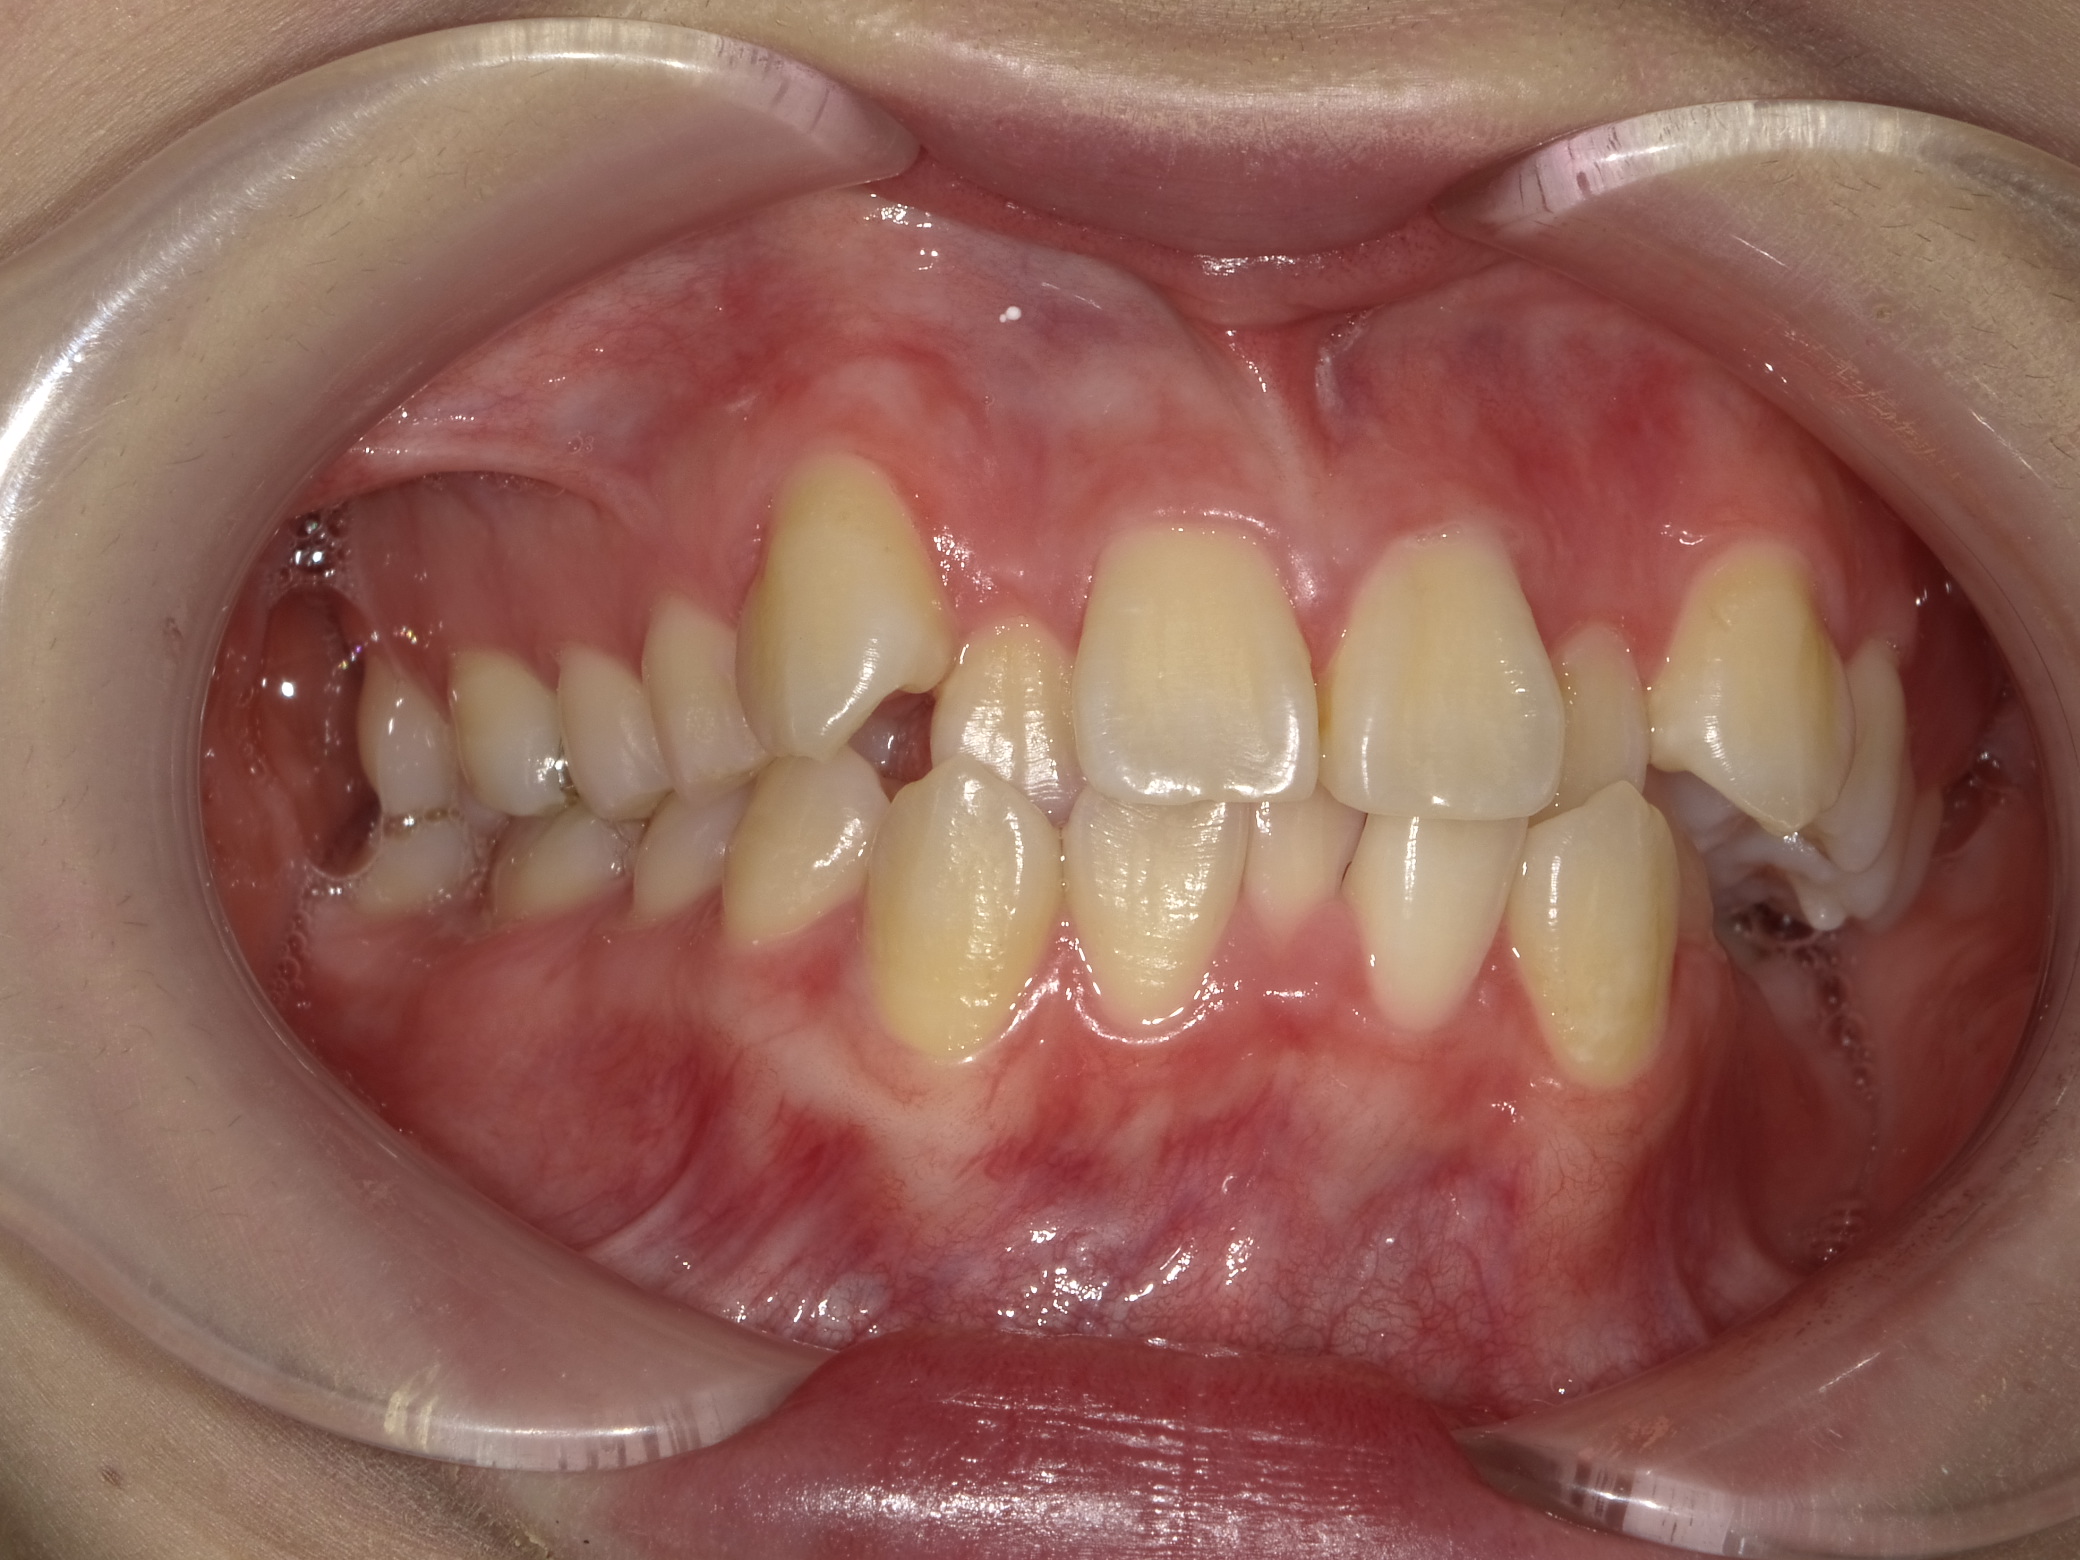

写真のとおり、①八重歯を目立ち、②上の2番目の歯が下の前歯に対して内側に傾いて、全体的にバラついているのですが、一番の問題は、

上の写真にあるとおり、左側がほぼ噛み合っていない点です。

この噛み合わせが原因で左右のバランスおよび顔の輪郭すら左右差が生じてきます。

右側の噛み合わせと比べるとその差は歴然です。